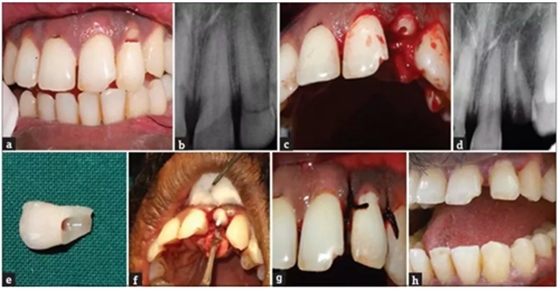

病例1

患者,男,23岁,因跌倒在地导致左侧上颌侧切牙复杂冠折。患牙无明显松动,口内和口外检查无明显软组织创伤。牙齿22出现EllisⅢ级牙折,牙折线从舌侧中1/3至舌侧龈下2mm处。折断部分松散地附着在牙齿上。

a. 术前口内照片;b. 术前根尖片;c. 拔除牙齿折断片;d. 根尖部分充填;e. 牙齿折断片;f. 折断片再复位;g. 软组织缝合;h. 术后2年。

根尖片显示牙根发育完全,无嵌入。患者希望保留牙齿,计划给予患者根管治疗和桩核修复。

局部麻醉后,轻轻去除患牙折断部分,并放入生理盐水中防止脱水和变色。仔细检查折断片与患牙的适应性。根尖定位仪确定根管工作长度并拍摄根尖片确认,扩孔钻进行根管冠部扩大,根管在工作长度上扩大到60#。在制备过程中使用约3%的次氯酸钠冲洗、将根管用指尖干燥并用根管封闭剂封闭,牙胶尖充填根管,根管口临时修复体密封。牙髓治疗完成后的第二天,局麻下翻瓣,暴露腭侧龈下断缘。去除根管冠部2/3部分的牙胶,预备桩道。试纤维桩,并调到合适的长度。对折断部分的牙折片髓室部分进行预备以容纳纤维桩的冠部及核。然后用37%磷酸酸蚀,冲洗、干燥后涂布粘结剂。使用双固化树脂粘结剂(RelyX, 3M, )将桩置于根管中,经过适当的色调匹配后,冠部折断片内部进行酸蚀并用可流动复合树脂粘结到牙齿上。最后,皮瓣复位,缝合,检查咬合并给予患者术后指导。术后1月,3月,6月,1年,2年进行临床和影响学检查,牙齿愈合良好。